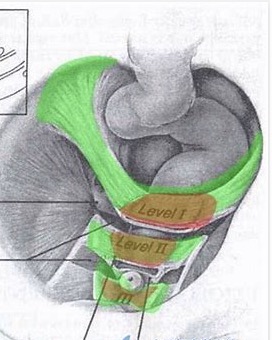

- 妇产康复―盆底结缔组织的功能解剖,三水平理论、三腔系统 布骨产后恢复中心 ,2020-04-19

- 发挥支撑作用的结缔组织包括盆腔内筋膜、盆腔韧带及会阴隔膜。盆腔内筋膜是腹横筋膜延续至覆盖骨盆底,位于盆底肌之上,腹膜之上,包绕盆腔脏器并将其连接至支持的肌肉组织和骨盆的骨组织。这一结缔组织网与盆腔脏器表面的结缔组织纤维相交织,使盆腔脏器固定在正常解剖位置。盆腔内筋膜的特殊部位增厚形成了盆腔韧带,参与.....

- 妇产康复---盆底解剖结构及肌肉群 BuGu ,2020-04-19

- 盆底解剖结构,女性盆底是由封闭骨盆出口的多层肌肉和筋膜构成,有尿道、阴道和直肠贯穿其中。盆底肌肉群、筋膜、韧带及其神经构成了复杂的盆底支持系统,其互相作用和支持,承托并保持子宫、膀胱和直肠等脏器在盆腔的正常位置。若盆底结构和功能发生异常,可影响盆腔脏器位置及功能,甚至引起分娩障碍,而分娩处理不当,亦.....